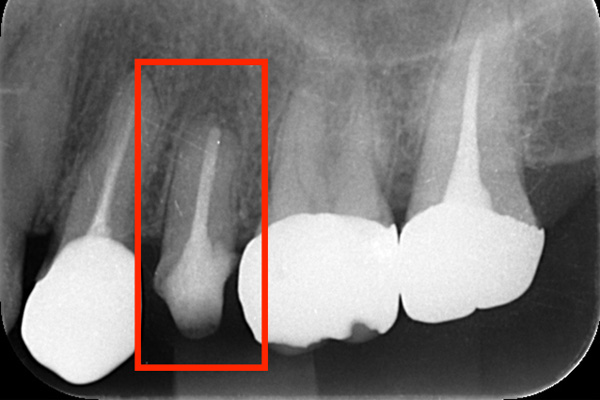

左のレントゲンでは破折したかどうかはわからないが、虫歯になっている部分をとっていくと歯が割れているのがはっきりとわかりました。

歯が割れるケースで多いのが金属の土台(メタルコア)が入っている場合です。特に根の中に長いものが入っていると、歯を割る力が強くかかるため、割れることが多いです。